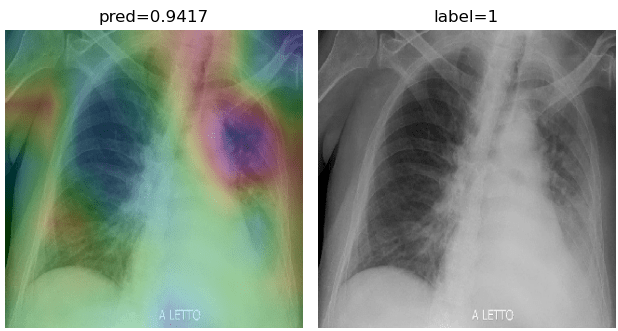

To overcome the aforementioned issues and force the model’s attention to the correct regions of interest (ROIs), we introduce the COVID-CXNet. Our model is initialized with the pretrained weights from CheXNet. A dataset of 3,628 images, 3,200 normal CXRs and 428 COVID-19 CXRs, are divided into 80% as training-set and 20% as test-set. Batch size is set to 16, rather than 32 in previous models, regarding memory constraints. Grad-CAMs of the COVID-CXNet for random images are plotted in Fig. 15.

Figure 15: Grad-CAM visualization of the proposed model over sample cases

More Grad-CAMs are available in Appendix A. Heatmaps are more accurate than previous models, while an accuracy of 99.04% and an f-score of 0.96 are achieved. Table 3 is the confusion matrix of the proposed model.